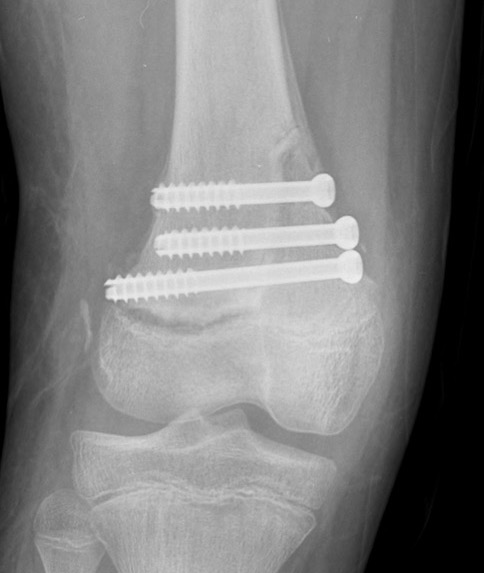

Salter Harris Type II with large Thurston Holland fragement

Distal Femur Salter Harris 2Distal Femur Salter Harris 2

Technique

AO foundation screw fixation Salter Harris Type II

AO foundation medial approach to pediatric knee

AO foundation lateral approach to pediatric knee

Reduction

- attempt closed

- may be periosteum blocked on tension / medial side

Medial subvastus approach to knee

- identify Thurston-Holland fragment

- physeal sparing metaphyseal screws

Distal Femur SH2 ORIFDistal Femur SH2 ORIFDistal Femur SH2 Lateral